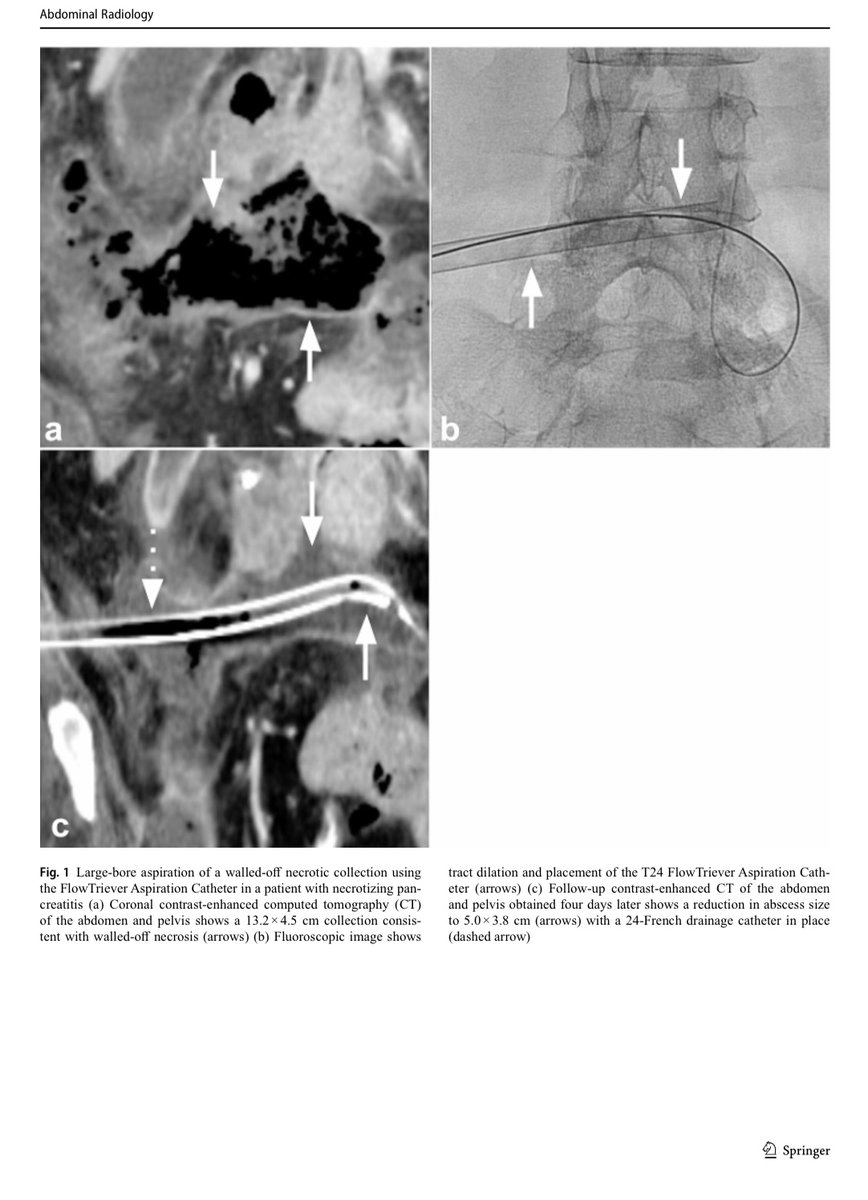

The FlowTriever aspiration catheter may be used off-label for complex non-vascular collections refractory to standard drainage, allowing effective debris removal with drain placement and potential resolution, though cost-effectiveness requires further study. @USC @InariMedical

Mechanical aspiration with the FlowTriever Aspiration Catheter may be an alternative or adjunct to catheter upsizing and fibrinolytic therapy for complex intra-abdominal abscesses, especially when drainage fails. https://t.co/hr08aRaZ8o @InariMedical @CVIR_Journal @JVIRmedia